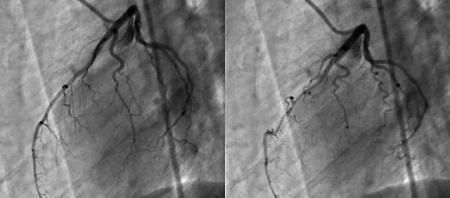

Ma parlavo dei miei hobbies preferiti: ne ho uno che ve lo raccomando, la Coronarografia. Oh, c'è a chi piacciono i francobolli, la pésca, le armi antiche o il salto triplo, e a me piace la coronarografia. Mi ci mandano la mattina dopo, sabato venti ottobre, ad un altro ospedale dall'altra parte della città, perché quello mio, di zona, non è attrezzato per farla. Ci vuole la Sala di Emodinamica; quindi arriva l'ambulanza infermieristica, ed eccomi infine pronto, nudo come un verme, per farmi allegramente sfruconare dentro la sentimental pompa cardiaca di cui sono indegno titolare da svariati decenni. Steso su un lettino rigido, mi viene prima infilato senza tante cerimonie un sondino nel braccio destro, a partire dal polso; segue l'introduzione del vasodilatatore, che per tre secondi ti rende un novello Muzio Scevola dato che sembra di infilare il braccio in un braciere ardente; poi entra il mezzo di contrasto, e infine la fibra ottica manovrata da un simpatico e bravo medico cardiologo di mezz'età dal nome ancor più simpatico e che si esprime in fiorentino di campagna. Su una parete di monitor, Riccardo, per la quarta volta, ricomincia a vedere il Riccardo interno, quella roba che si ha dentro dalla nascita fino alla morte ma che non si vede mai, pur essendo a pochi centimetri di distanza. Il Viaggio Allucinante: si immagina il sottomarino di Asimov che sta per sbucare da un momento all'altro, e invece sono le proprie coronarie. In una di queste si era formato un grumo di sangue, proprio in mezzo a uno degli stent del 2011. Un trombo bello e buono. Si risente pronunciare una parola forse un po' desueta attualmente, ma che fa sempre venire qualche sudorino freddo: O Riccardo, t'ha' aùto una trombòsi, bisogna leà qui' trombo, 'un ti preoccupà se ora 'e tu senti un po' malino, ti s'interrompe i' flusso, se ti senti andà' 'un ti preoccupà, lo deve fare. Meraviglioso, quel “lo deve fare”: è la stessa frase che dice il meccanico, quando sente il rumorino strano nel motore. In fondo, siamo macchine.

In effetti, per un momentino mi sento proprio andare; ma, tanto, lo deve fare. Sento un male boia, dato che, in pratica, si tratta di un infarto sia pure indotto e controllato. In quella posizione sul rigido, in più ho un mal di schiena atroce e mi devono fare due siringate di morfina. Nel frattempo mi spiegano che il mio sanguino, nonostante gli antiaggreganti e anticoagulanti che prendo da anni, è bello denso e marmellatoso, e che quindi è soggetto a formare grumi e trombi. In parole povere, sono un vecchio arteriosclerotico (si dovrebbe dire aterosclerotico, però). Mi levano il trombo, alla fine; tutto bene, complimenti (e per cosa, mi chiedo?), ora si va in terapia intensiva qui accanto e ti si fa anche tanta bella eparina. Cos'è l'eparina? Nei casi come il mio, va familiarmente sotto il nome di “Idraulico Liquido”, o “Anitra WC”. Stasa. Per un po' divento Heparinik, il Diabolico Vendicatore.